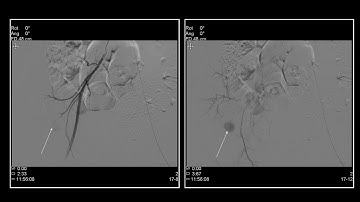

nBCA glue embolization of a post-pyelonephritis renal pseudoaneurysm